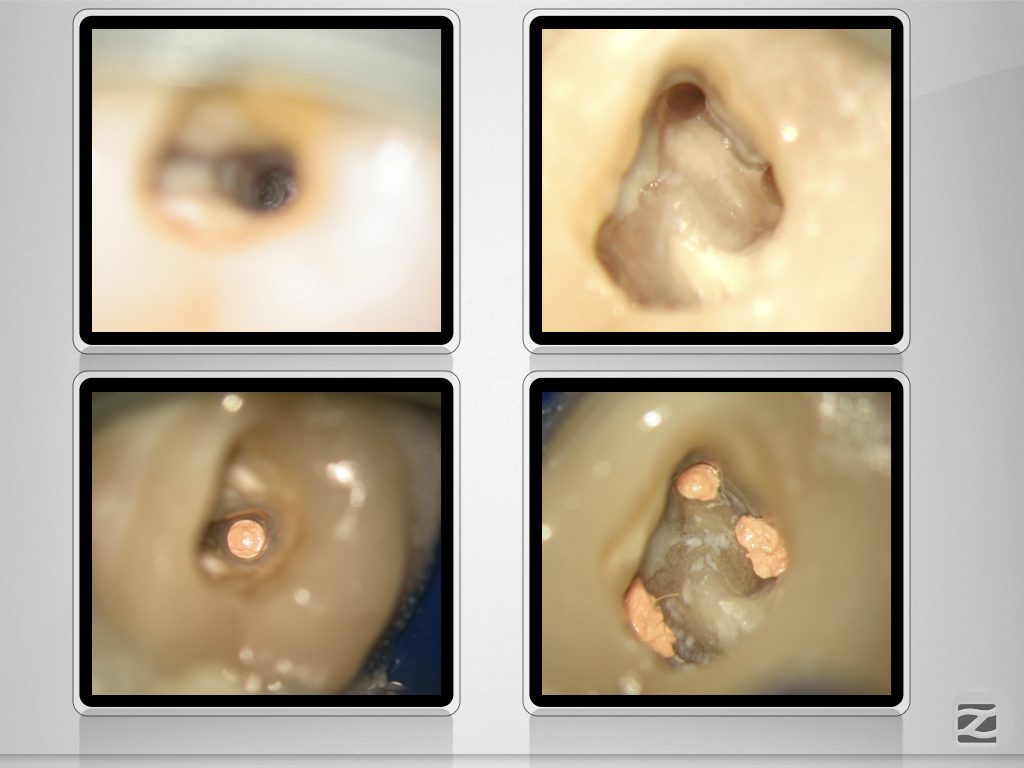

26D.009 Veröffentlicht 12. Februar 2021 am 1024 × 768 in Tiefe Aufgabelung, zwei Fisteln und ein Recall